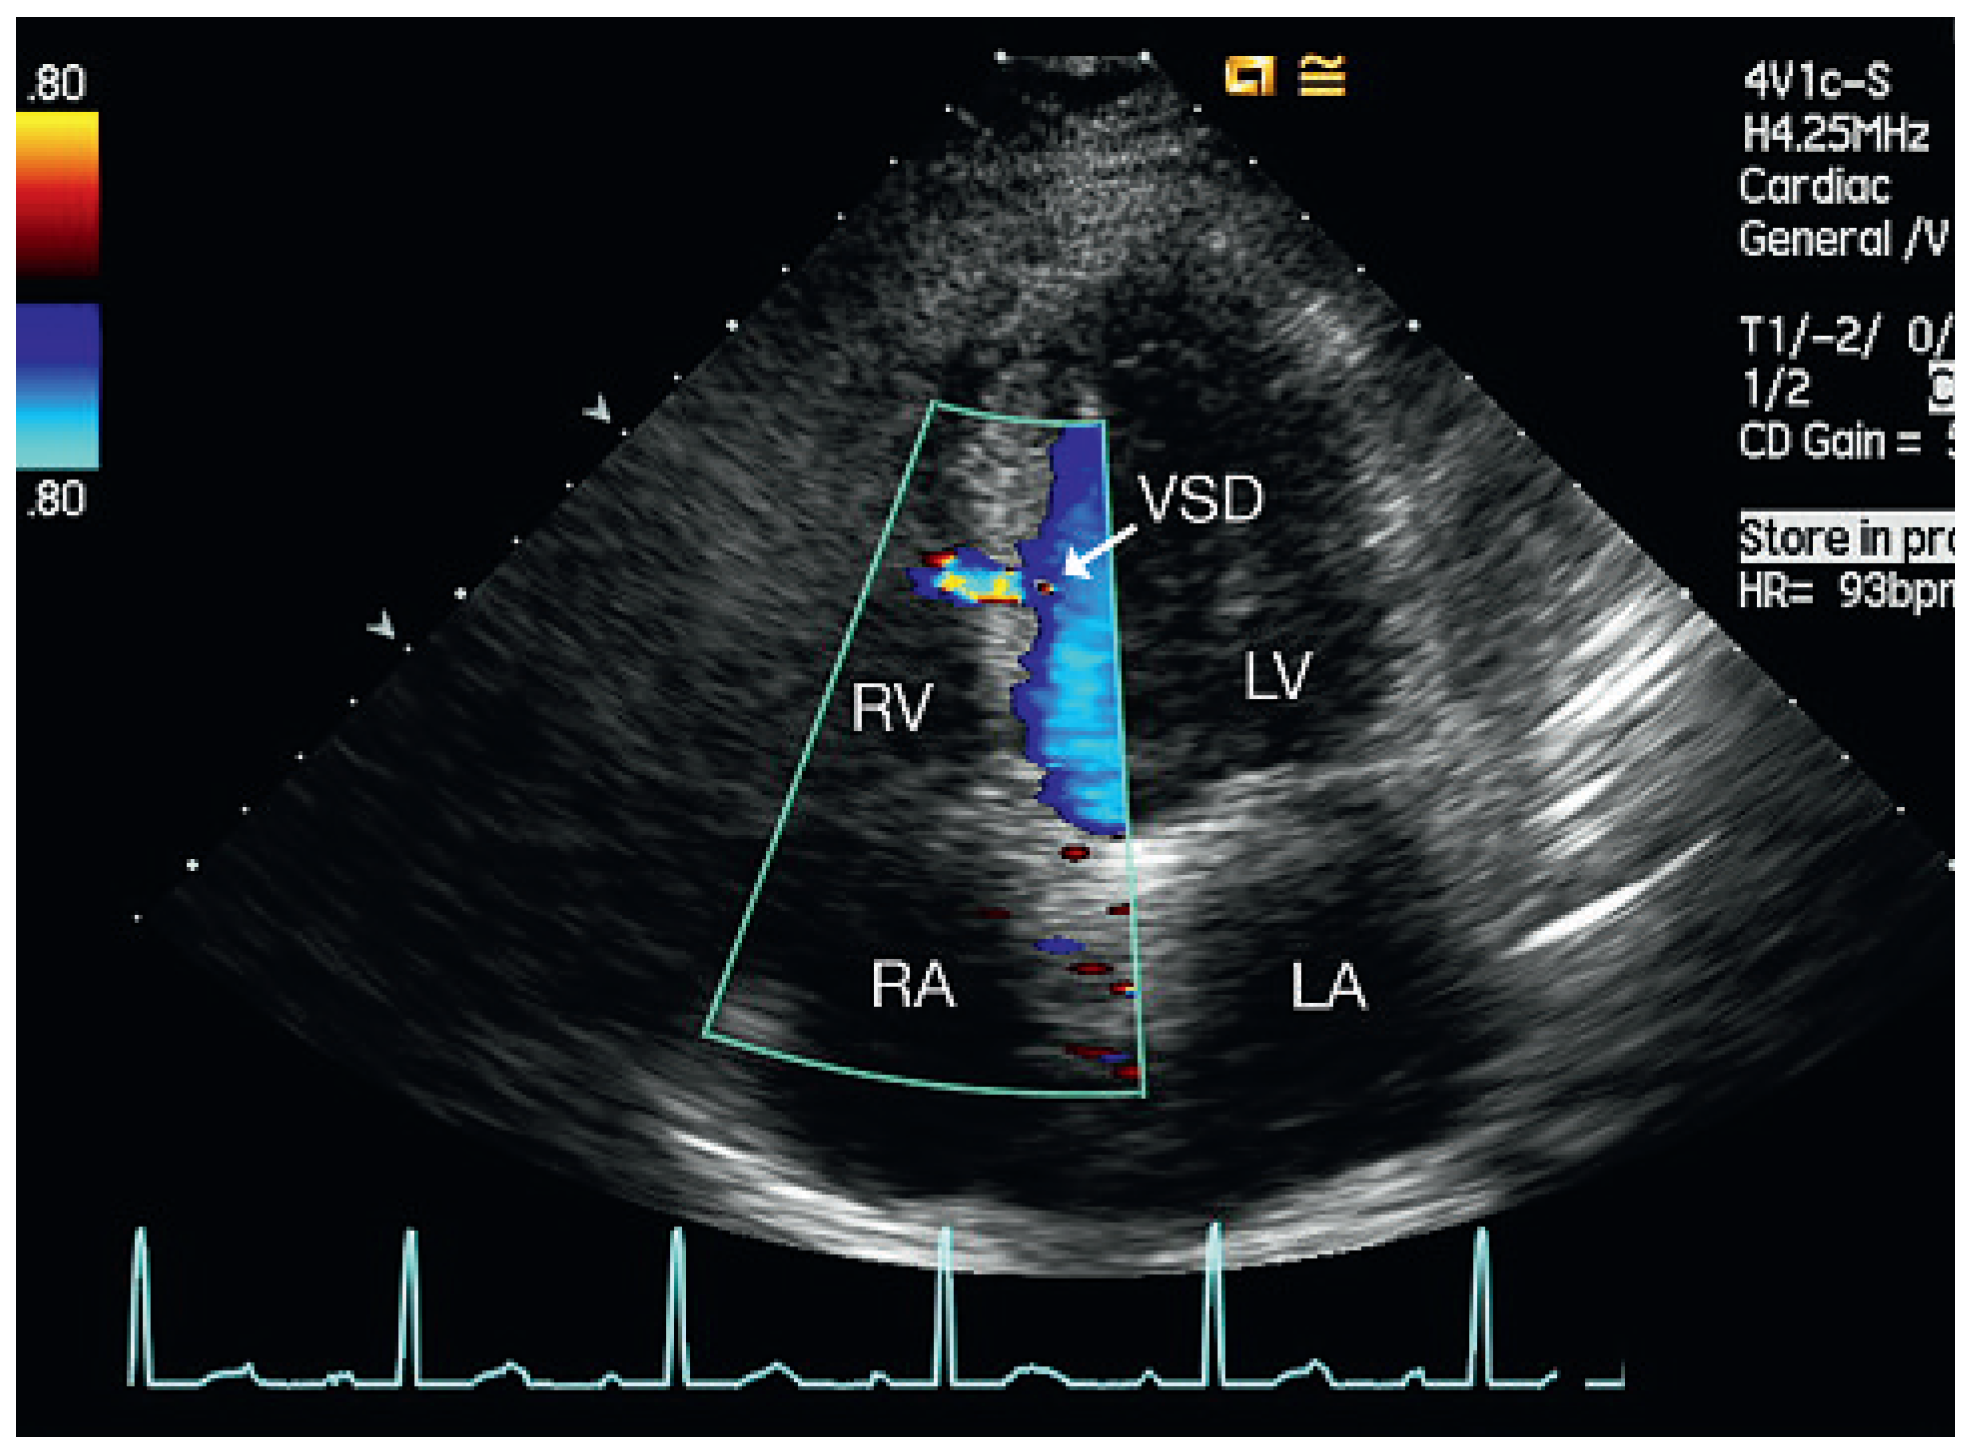

Figure 1.

Patient 1, at admission. Four-chamber view: muscular VSD mid-septal. LA = left atrium; LV = left ventricle; RA = right atrium; RV = right ventricle; VSD = ventricular septal defect.

From September 2007 to December 2008, five patients aged 54–69 years were admitted to our institution for cardiac rehabilitation after surgical cardiac valve replacement (Table 1). Successful replacement of the aortic valve was performed in four of the patients and mitral valve replacement in the other. All patients received mechanical prosthetic valves (ATS medical) and had a history of dyspnoea, fatigue and exercise limitation. Physical examination on admission did not reveal signs of congestion in any of the patients. The admission electrocardiogram showed sinus rhythm or atrial fibrillation (patient 4) and signs of left ventricular hypertrophy in 3 of 5 patients. Doppler echocardiography revealed a restrictive muscular ventricular septal defect (Figure 1, Figure 3, Figure 4, Figure 5 and Figure 6) with Qp/Qs < 1.4 in all of the patients. The function of the prosthetic valves was normal and in one patient (patient 5) systolic pump function was moderately reduced.

Echocardiographic follow-up revealed spontaneous closure of the septal perforation in four of the five patients (Figure 2). In one patient the septal defect persisted for one and a half years after surgery, but he remained asymptomatic without deterioration of left ventricular function or increased pulmonary artery systolic pressure.